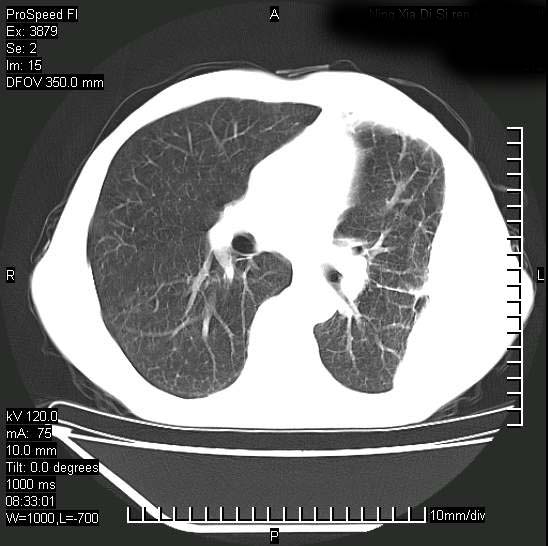

以下是引用37度在2008-6-6 11:20:00的发言:[br]1.包裹性积液,多考虑结核性;[br]2.穿刺术后改变。

以下是引用312nanyang在2008-6-6 15:12:00的发言:[br]基本支持楼主意见[br]疑问?左下肺支气管旁的软组织(16层)密度怎么解释?淋巴结还是斜裂胸膜增厚所致?能否增强进一步检查